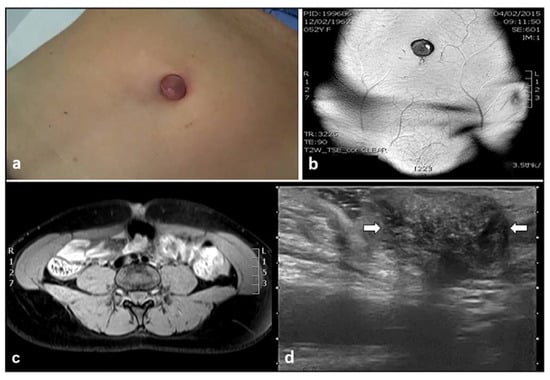

3. Umbilical Endometriosis